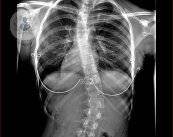

Escoliosis, ¿cómo detectar el problema en los niños?

La escoliosis es una deformidad de la columna vertebral que provoca una curva en el plano frontal y en el lateral. El Dr. García Fontecha te explica en qué consiste y cómo puede detectarse en los niños.